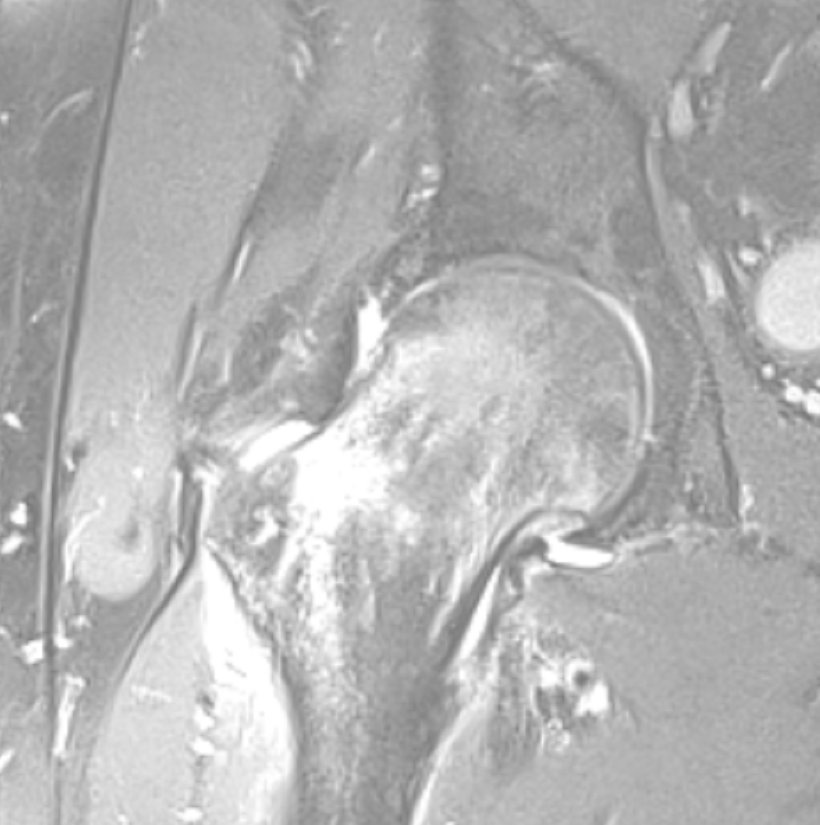

Ασθενής με οστικό οίδημα αριστερού ισχίου

Ασθενής 51 ετών, με αιφνίδιο άλγος από μηνός συνεχώς επειδυνούμενο. Η μαγνητική τομογραφία έδειξε ότι υπάρχει εκτεταμένο οστικό οίδημα αριστερού ισχίου (βέλος). Πραγματοποιήθηκε έγχυση ισχίου με υαλουρονικό και παυσίπονα. Ο ασθενής ένιωσε άμεσα ανακούφιση με πλήρη υποχώρηση των συμπτωμάτων που διατηρείται έως σήμερα 1.5 χρόνο μετά.